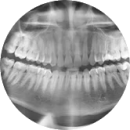

Для постановки точного диагноза и назначения схемы лечения специалисту необходима полная картина состояния Вашего здоровья на момент посещения нашей клиники. Все назначения, которые Вы получаете в “АЙСБЕРГ”, в том числе направления на анализы и другие диагностические исследования, выполняются в объеме не менее предусмотренных стандартом Минздрава РФ. Для постановки, снятия или подтверждения диагноза, назначения лечения или диагностики могут понадобиться дополнительные исследования, которые назначает врач.

Все эти меры направлены на то, чтобы с помощью высокоточной и всесторонней диагностики оказать Вам необходимую стоматологическую помощь, разработать эффективную и щадящую программу лечения или действенную программу профилактики!